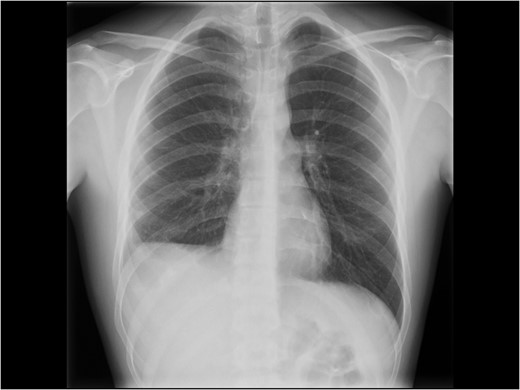

Chest X-ray at follow-up. Still some degree of diaphragm high-stand on the right side.

Due to the delayed presentation and concomitant presence of a subacute liver injury with fragile tissue, the decision to delay elective treatment of the diaphragm was made. The patient was admitted 8 weeks later for elective repair. An initial laparoscopic approach was attempted, but was converted to open repair by an inverse L subcostal incision due to the size of the defect and adhesions of diaphragmatic edges on surfaces to the liver. In addition there were pulmonary adhesions to the posterior liver surface (Fig. 3A). Adhesiolysis was performed of the diaphragmatic defect to the liver. A double lumen ventilation tube allowed for deflating of the right lung and gentle dissection of the pulmonary adhesions to the liver. Considerable loss of tissue domain of the diaphragm due to retraction and fibrosis was noted (Fig. 3B) for a grade V diaphragm injury (Table 1) based on the AAST score [5]. The size of the defect, measured as 10 cm × 5 cm (50 cm2) prevented primary suture repair of the diaphragm in an end-to-end fashion. Thus, a 1 mm thick Gore-Tex™ patch was used to cover the defect (Fig. 2A) and a pulmonary drain was placed (Fig. 4B). The patient recovered uneventfully, the chest drain was removed on post-operative Day 2 and he was discharged on post-operative Day 6 with a recommendation not to resume full physical activity until 2 months after surgery. When he was seen in the outpatient clinics 3 months later postoperatively, he had resumed full physical activity including sports. He had no complaints and had a well-healed scar. An erect chest X-ray showed a moderately high-standing diaphragm on the right side (Fig. 5).